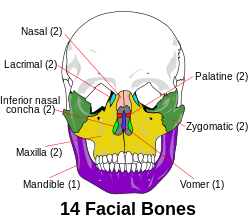

Facial skeleton

| Facial bones | |

The fourteen bones that form the human facial skeleton. | |

For the human skull, most sources always include these fourteen bones in their lists of facial bones:[1][2]

- Inferior nasal concha (2)

- Lacrimal bones (2)

- Mandible

- Maxilla (2)

- Nasal bones (2)

- Palatine bones (2)

- Vomer

- Zygomatic bones (2)